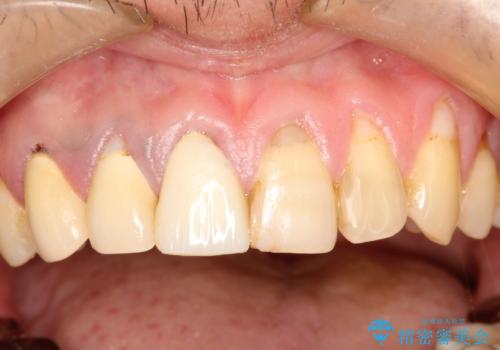

- 以前治療した上の前歯の不自然な保険のかぶせ物を自然なものにしたいとのことで来院されました。

右上の前から1番目から3番目までの歯のかぶせ物を土台から再治療することとなりました。